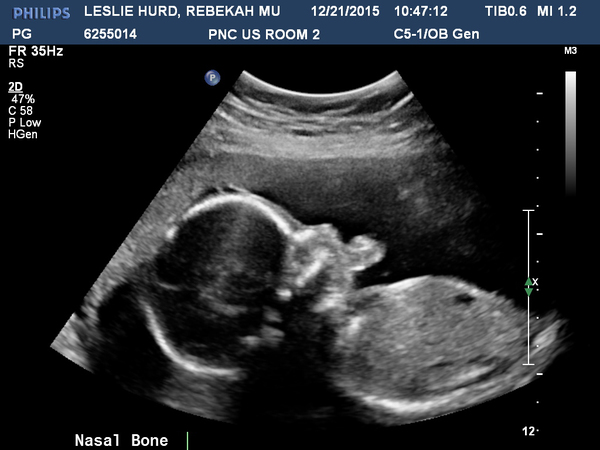

21 Week Ultrasound

10:00:00       Monday 21 December 2015